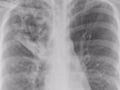

ますます寒くなるこれからの季節、注意したいのが肺炎。でも困ったことに、お年寄りの場合はなかなか発見しにくいのです。ちょっと風邪気味みたいだけど、平熱だし・・・と思っていたら、じつは「肺炎だった」というケースも多々あります。いったいどうして、こんなことが起こるのでしょうか?

ところがお年寄りの場合、このサイトカインの分泌に異常が起こっている場合があるのです。そのため、体温も上がらず、ウイルスは暴れっぱなし――という困った状態に陥りがち。平熱にもかかわらず、じつはひそかに肺炎症状が進行しているかもしれません!体温チェックだけで安心してはいられないのです。